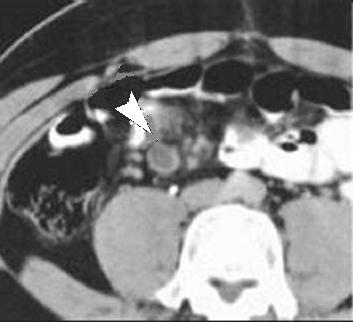

Aspect d'une diverticulite de Meckel .

Diagnostique differentiel facile avec appedicite

meso-coeliaque aigue par sa location a distance du

coecum . |

Divereticulite de

Meckel severe correspondant a une perforation

bouchee de la diverticule : Image infiltration de

graisse peri diverticulaire et la presence de gaze

extra digestif par la perforation bouche a temoin (

fleche blanche ) . |